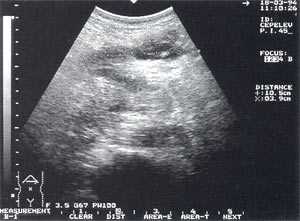

- изменение эхогенности железы: повышение - 85,6% случаев (рис. 2); нормальная - 8,6% случаев; понижение - 5,8% случаев.

Рис. 2. Острый панкреатит, повышение эхогенности поджелудочной железы (по сравнению с эхогенностью печени).